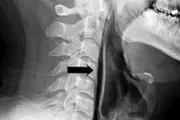

پارگی گلو مرد بیچاره بخاطر عطسه اشتباهی!+ عکس

اشتباه مرد 43 سال هنگام عطسه برایش گران تمام شد ، لحظاتی بعد دردهای شدید و حالت غیرقابل تحمل در بلع او را راهی بیمارستان کرد.